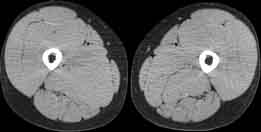

Visible Human male: Sectio transversalis 2073

CT